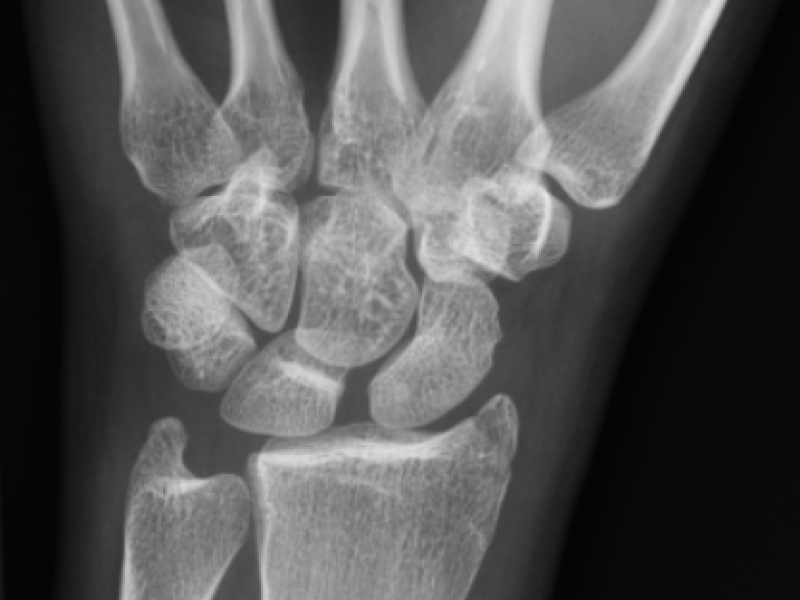

A 21 yo F presents with L wrist pain after falling forward